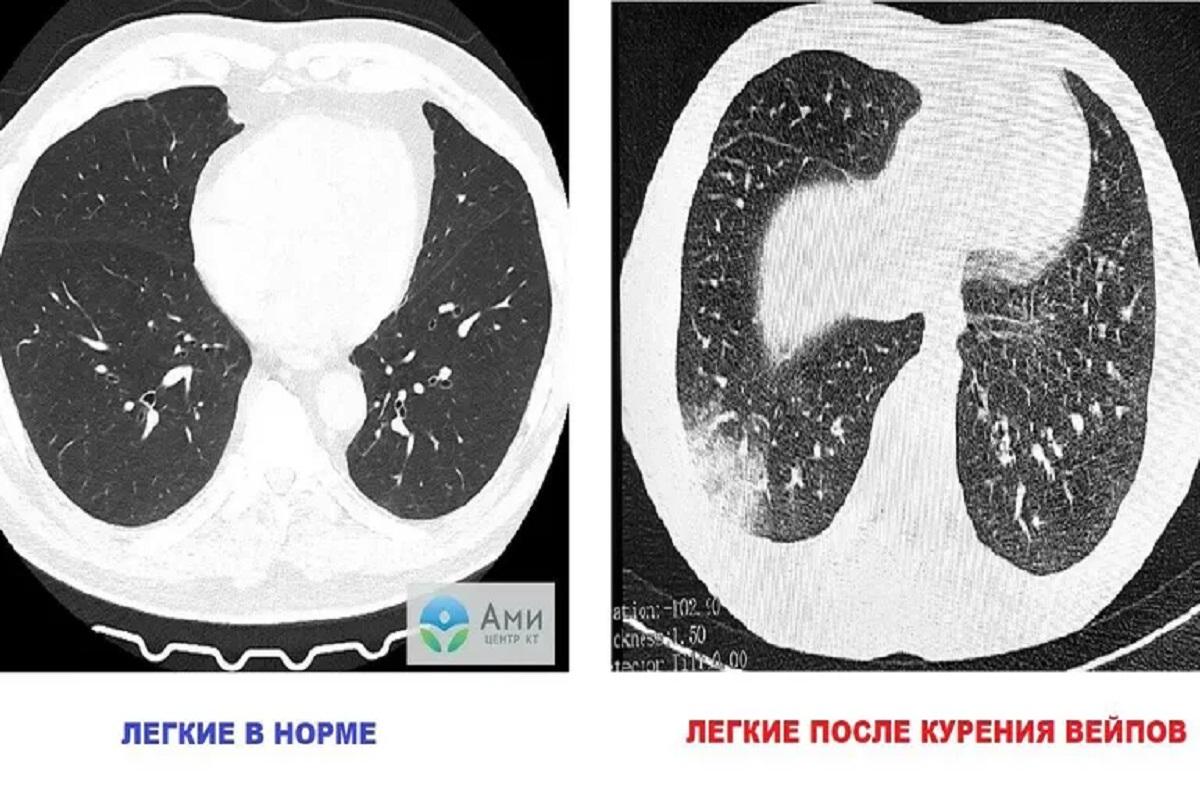

Ученые изучили влияние вейпов на организм и пришли к выводу, что электронные сигареты могут вызвать острое воспаление легких – EVALI.

В результате токсины накапливаются в легких, вызывая воспаление и нарушение газообмена в альвеолах. В последующем развивается EVALI, которое проявляется одышкой, лихорадкой, болью в груди, тошнотой, рвотой и сильной усталостью, рассказал врач «Известиям».